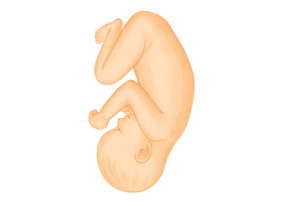

●体が大きくなるため、多くの赤ちゃんは広い骨盤の中に、大きな頭やおしりを入れて、縦の向きになります。

赤ちゃんは横隔膜を上下させる呼吸様運動をしています。これは外界に出たときの呼吸の動きに似ています。聴覚がほぼ完成し、赤ちゃんへ語りかけるチャンスです。体も成長し、縦向きに位置するでしょう。

後期になると赤ちゃんは頭を下にした姿勢に落ち着きますが、なかには足が下になるさかごになる赤ちゃんもいます。でも、さかごは決して珍しいものではありません。お産のときまでに自然に治ることが多く、医師の指導のもと、直す方法もいくつかあります。

妊娠30週ごろになると、おなかの中で赤ちゃんは頭を下にしている(頭位)のが一般的です。これに対して、足やおしりが下になっている状態が「さかご(骨盤位)」です。さかごが問題になるのはこの30週以降。原因は、胎児側と母体側に分かれます。胎児側では多胎妊娠や羊水過多など、母体側では前置胎盤などの胎盤の位置の問題、子宮筋腫がある、子宮奇形などが考えられますが、原因がわかっているのはほんの一部で、原因がわからないことも多いのです。